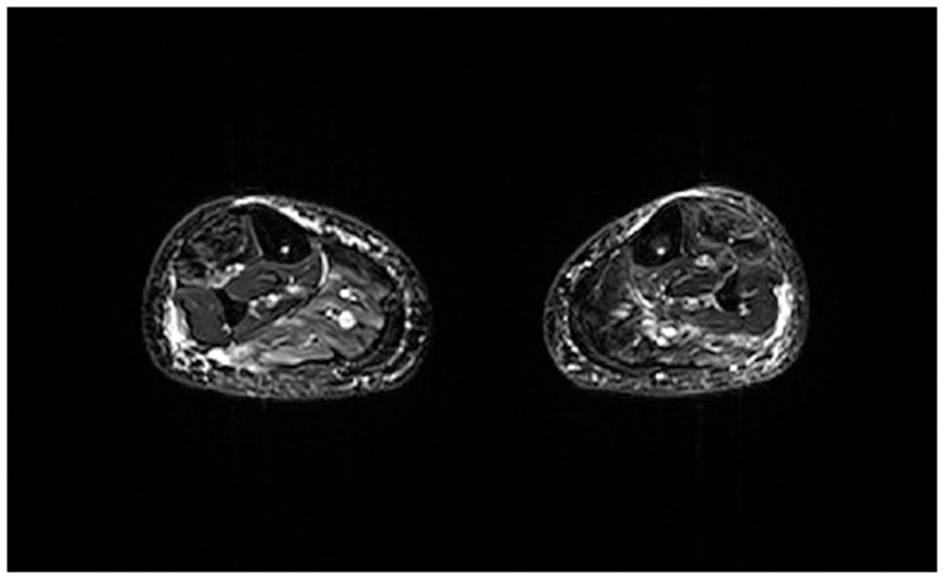

Twenty-five FSHD patients (10 females, age range: 19–60 y) and six healthy volunteers (HCs) (5 females, age range: 47–63 y) were scanned on a 3T MRI scanner (Magnetom Skyra, Siemens Healthcare, Erlangen, Germany) using integrated spine and body surface coils. Acquisition volume was centered on the calf with the last acquired slice located at 6 cm proximally from the upper limit of the patella. The MRI protocol included 3D 6-point multi-echo gradient-echo (MEGE) [52 slices, slice thickness = 5.0 mm, distance factor = 20%, resolution = 1 × 1 × 5 mm3, TR/ TE = 35 ms/1.7–9.2 ms, scan time = 15 min], multi-echo spin echo (MESE) [7 slices, TH = 10 mm, DF = 300%, resolution = 1.2 × 1.2 × 10 mm3, TR/TE = 4,100 ms/10.9–185.3 ms, 17 echoes, scan time = 5.13 min] and 2D STIR sequences [50 slices, TH = 5.0 mm, DF = 20%, resolution = 1 × 1 × 5mm3, TR/TE = 4,200/82 ms, TI = 230 ms, scan time = 3.40 min]. An example of STIR image is reported in Figure 1. Pre-processing steps have been performed on STIR images in order to ensure features extraction on an inter-patients harmonized grayscale values. In particular, all images were pre-processed by 3DSlicer (26) N4 Bias Field Correction to correct low frequency intensity non-uniformity in MRI images, and 3DSlicer Histogram Matching to normalize grayscale MRI images.

Figure 1

Example of axial STIR image of an FSHD subject at calf level. Image acquired at Neuroradiology Department of IRCCS Mondino Foundation.